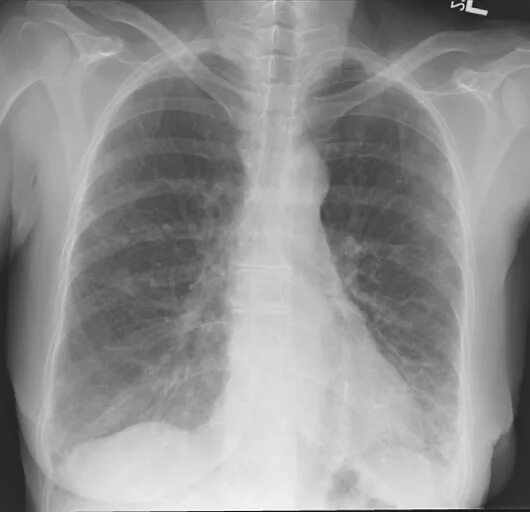

Пневмосклероз фиброз легких